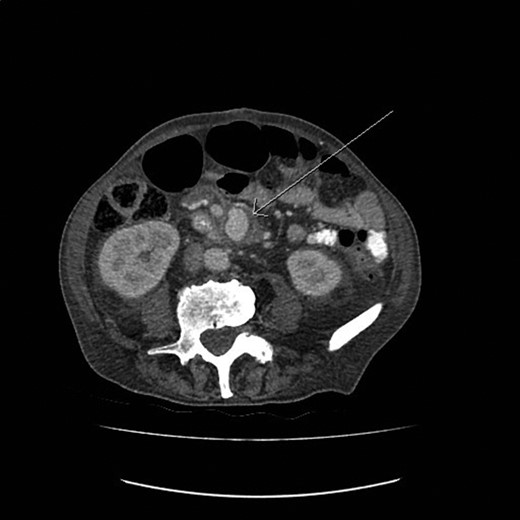

A 77-year-old man with past medical history of atrial fibrillation, hypertension and diabetes mellitus (Type 2) presented to the emergency department with 6-week history of supra pubic/left iliac fossa pain and 14-kg weight loss. On examination, he was found to be a febrile with distended but nontender abdomen. His laboratory data showed a new onset normocytic anemia (Hemoglobin 7.0 g/l) and normal inflammatory markers (white blood cell count 7.6 × 109/l, C-reactive protein 22 mg/l). Due to the nonspecific nature of the abdominal pain and weight loss a computed tomography (CT) with contrast was performed. This demonstrated an incidental finding of a 4.4 × 3-cm SMAA. This was associated with mesenteric edema and stranding and multiple local lymphadenopathies (Fig. 1).

The CT image demonstrating a SMAA measuring 4.4 × 3 cm in size.